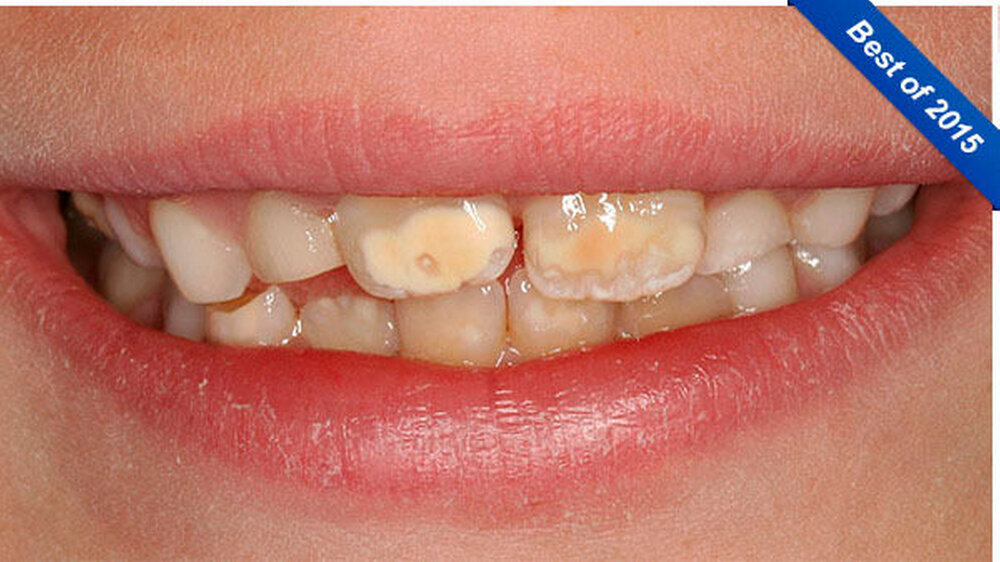

Die Patientin wies im Frontzahngebiet an den Vestibulärflächen der mittleren Oberkiefer-Inzisivi deutlich abgrenzbare milchig-weiß bis dunkelgelb-orange Opazitäten auf. Inzisal der Opazitäten zeigten sich weniger gut abgegrenzte milchig-weiße Opazitäten mit teils wolken-ähnlicher Struktur, teils linien-förmiger Art. Die lateralen Oberkiefer-Inzisivi waren noch nicht durchgebrochen. Weiterhin fanden sich weniger auffällige Opazitäten an den Unterkiefer-Inzisivi, insbesondere an den Zähnen 31 und 42. Außerdem wies der Zahn 83 im inzisalen Anteil eine Opazität auf (Abbildung 1).

Zusätzlich zu den Frontzähnen waren die Molaren in sehr unterschiedlicher Ausprägung betroffen. Dies reichte von lediglich kleineren Opazitäten bis zu darüber hinausgehenden Schmelzverlusten: Im ersten Quadranten war Zahn 16 klinisch vollkommen unauffällig, hier zeigte aber der zweite Milchmolar insbesondere bukkal Opazitäten und Einbrüche des Schmelzes (Abbildungen 3 und 4) auf.